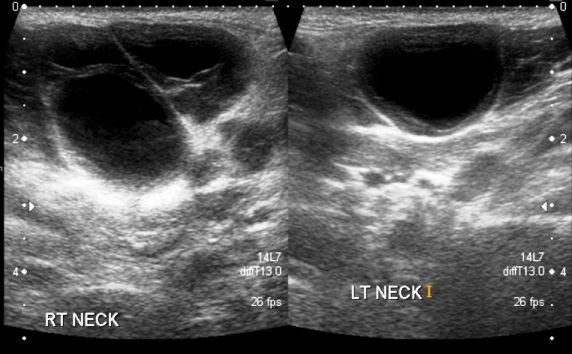

Ultrasound of the neck was ordered to determine the composition of the swelling. Findings included bilateral parotid masses identified as enlarged parotid glands with multiple 2- to 3-cm cysts present within the glandular tissue (Figures 1-3).

Figure 1. (Click each image to enlarge)